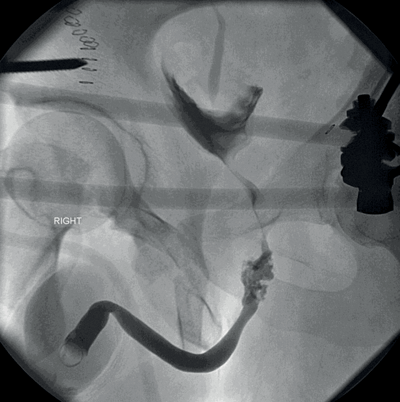

You have been called into the gynaecology operating theatre. They are performing a laparoscopic hysterectomy and suspect the right ureter has been injured.

1. Retrograde ureteropyelogram. Contrast extravasation, demonstrating an iatrogenic injury to the right lower ureter.

2. AAST ureteric injury severity scale.

Grade 1

Type of injury Haematoma

Description of injury Contusion or haematoma without devascularisation

Grade 2

Type of injury Laceration

Description of injury <50% transection

Grade 3

Description of injury ≥50% transection

Grade 4

Description of injury Complete transection with <2cm devascularisation

Grade 5

Description of injury Avulsion with >2cm of devascularisation

3. Surgical principles are: debride necrotic tissue, spatulate ureteral ends, water-tight mucosa-to-mucosa anastomosis with absorbable sutures, internal stenting and external draining. Grade 1 - Conservative +/- ureteric stent. Grade 2/3 - Ureteric stent +/- primary closure with suture. Grade 4/5 - Ureteric reconstruction.